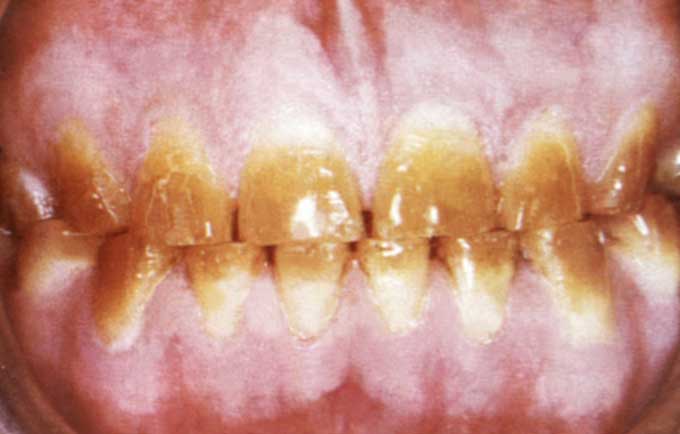

Если мать в третьем триместре беременности принимала даже незначительные дозы антибактериальных препаратов тетрациклинового ряда, то зубы малыша, формировавшиеся на тот момент приобретают неестественный оттенок – от желтоватого до коричневого.

Данная разновидность гипоплазии эмали считается системной, поскольку пигментации подвергаются все поверхности зубов.

На степень интенсивности окрашивания эмали влияют дозы, продолжительность курсового приема и вид попавшего в организм антибиотика:

- Небольшие дозы приводят к желтому, серому или коричневому окрашиванию;

- Значительные дозировки становятся причиной недоразвития эмали и появлению хорошо заметных при осмотре поперечных полос;

- Окситетрациклин вызывает менее заметные изменения, а прием диметилхлортетрациклина изменяет пигментацию очень интенсивно.

Чаще всего окрашена лишь часть коронки (пришеечная часть), но при высокой концентрации антибактериального средства пигментация имеет хаотичный характер.

Тетрациклиновые зубы — это разновидность системной гипоплазии зубной эмали, которая также известна как дисколорит. Проявляется в окрашивании зубов в серый, жёлтый, коричневый, реже — в бурый оттенок вследствие приёма антибиотиков тетрациклиновой группы (откуда и название патологии).